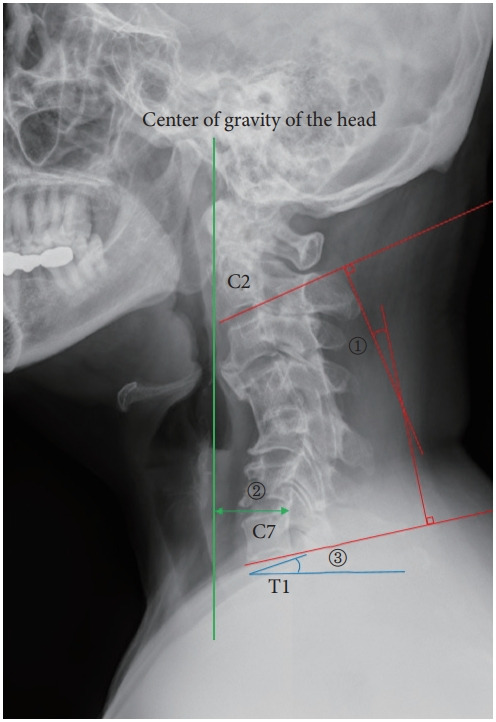

目的:分析后纵韧带骨化(OPLL)所致脊髓病和颈椎后凸患者行多节段前路截骨后路内固定后的长期临床和影像学结果。方法:接受多节段前路截骨后路内固定治疗opll性脊髓病和颈椎后凸的患者,随访时间至少为5年。分析术前、术后立即及最新随访时间点的临床结果(日本骨科协会颈椎病评分系统[C-JOA]、12项简短健康调查[SF-12]、颈部残疾指数[NDI])及影像学参数(C2-7前凸度、头部重心[CGH]-C7矢状垂直轴[SVA]、T1斜率)。结果:纳入28例患者。平均随访66.4个月。所有临床结果参数均有显著改善。C-JOA、SF-12和NDI在最新随访中均有显著改善(结论:多节段前路截骨联合后路内固定是一种安全有效的治疗opll性脊髓病伴颈椎后凸的手术选择。需要进一步的研究来调查手术后颈椎向前倾斜的情况。

Methods: Patients who underwent multilevel anterior osteotomy with posterior instrumentation for OPLL-induced myelopathy and cervical kyphosis and had a minimum of 5-year follow-up were included. Clinical outcomes (Japanese Orthopaedic Association score system for cervical myelopathy [C-JOA], 12-item Short Form health survey [SF-12], Neck Disability Index [NDI]) and radiological parameters (C2-7 lordosis, center of gravity of the head [CGH]-C7 sagittal vertical axis [SVA], T1 slope) were analyzed at the preoperative, immediate postoperative, and latest follow-up timepoints.

Results: Twenty-eight patients were included. The average follow-up period was 66.4 months. All clinical outcome parameters showed significant improvement. C-JOA, SF-12, and NDI showed significant improvement at latest follow-up (p<0.001). C2-7 lordosis increased significantly immediately postoperatively (-6.0°±10.4°) compared to preoperatively (+9.2°±9.6°), and was largely maintained at latest follow-up (-5.7°±9.4°). T1 slope significantly increased between the immediate postoperative timepoint (21.9°±7.7°) and latest follow-up (24.2°±9.5°) (p=0.046). CGH-C7 SVA significantly increased between the immediate postoperative timepoint (22.7±14.8 mm) and latest follow-up (32.2±22.6 mm) (p=0.046).